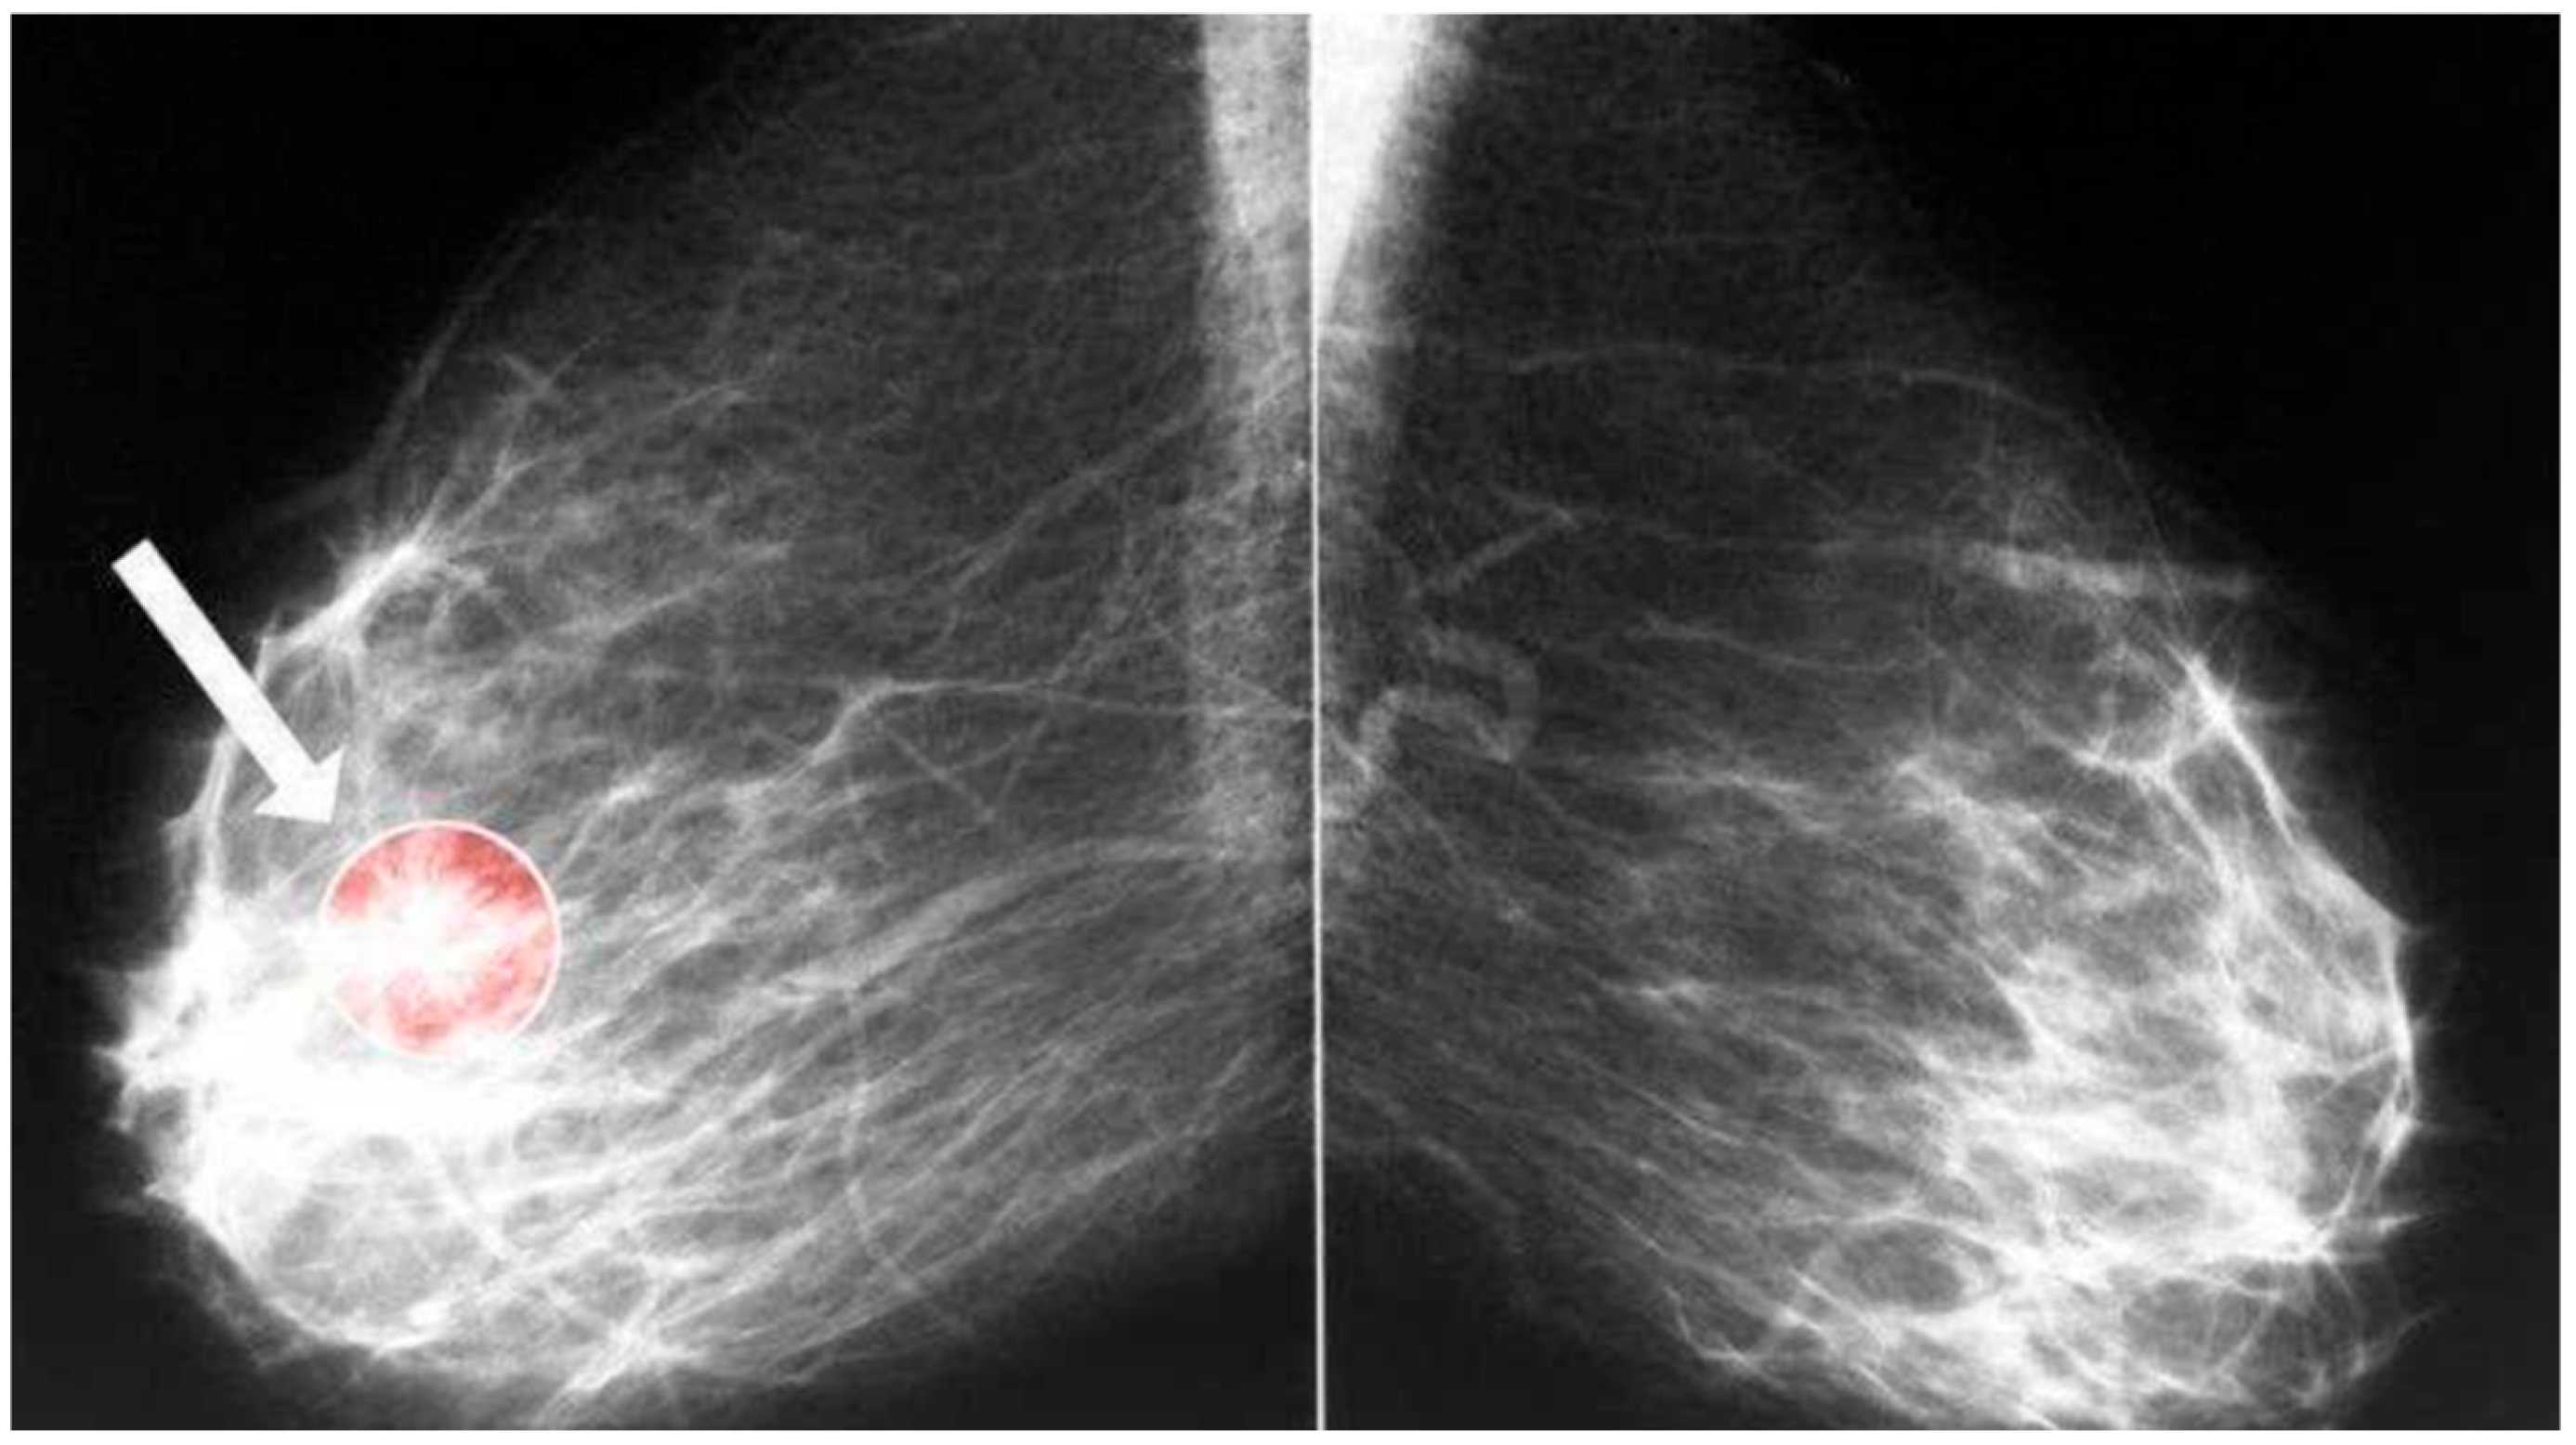

3.1. Datasets